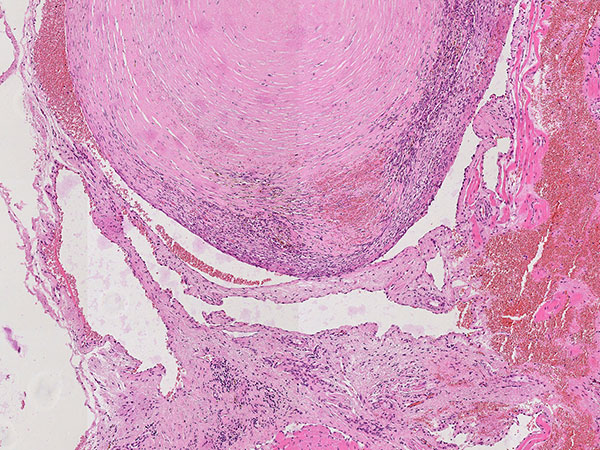

Hematoxylin & eosin stain, 21× magnification: A phlebolith already transformed into connective tissue is shown top right. Overall, as an indication of a vascular lesion, increased irregular vascular cavities are visible in the histopathological overview image.

Hematoxylin & eosin stain, 64x magnification: Layered, predominantly connective tissue appearance of the older, partially organized phlebolith. The phlebolith is surrounded by multiple proliferated, irregularly structured, thin-walled vascular spaces.